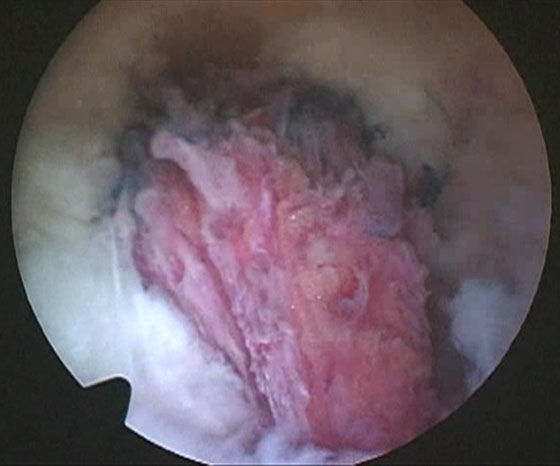

Se insufla el manguito neumático y se comienza la artroscopia por los portales anteromedial y anterolateral, se reconoce la lesión, se solucionan lesiones asociadas (meniscales, condrales, cuerpos libres) y se pasa a realizar el túnel femoral. Se localiza la hora 12 del intercóndilo, se visualiza la tróclea femoral y se ubica el sitio del túnel femoral (hora 1 rodilla derecha, hora 11 rodilla izquierda) (Fig. 2). Este túnel debe estar lo más alto posible en el intercondilo para colocar un injerto bien “vertical”. Realizamos este paso primero, haciendo el túnel desde el portal anterolateral, para evitar la dificultad de realizarlo después de la liberación capsular posterior que nos dejará menor cantidad de líquido intraarticular, y consecuentemente menor distensión dificultando la visión. Identificado el sitio de inserción, y sin resecar las fibras remanentes se coloca la fresa del diámetro a utilizar de manera de buscar que queden unos 3 mm desde la parte periférica proximal de la fresa hasta el cartílago articular del fémur, se pasa a través de la fresa canulada un clavo guía, se retira la fresa para confirmar la ubicación y se realiza el túnel de 20 o 25 mm de largo, de acuerdo al tipo de injerto que utilicemos. A continuación se ubica el espacio entre las fibras remanentes del LCP y el LCA, se debrida con shaver para dejar permeable este espacio, que nos permitirá más tarde traer el injerto desde la inserción tibial hacia la parte anterior de la rodilla (Fig. 3).

Figura 3